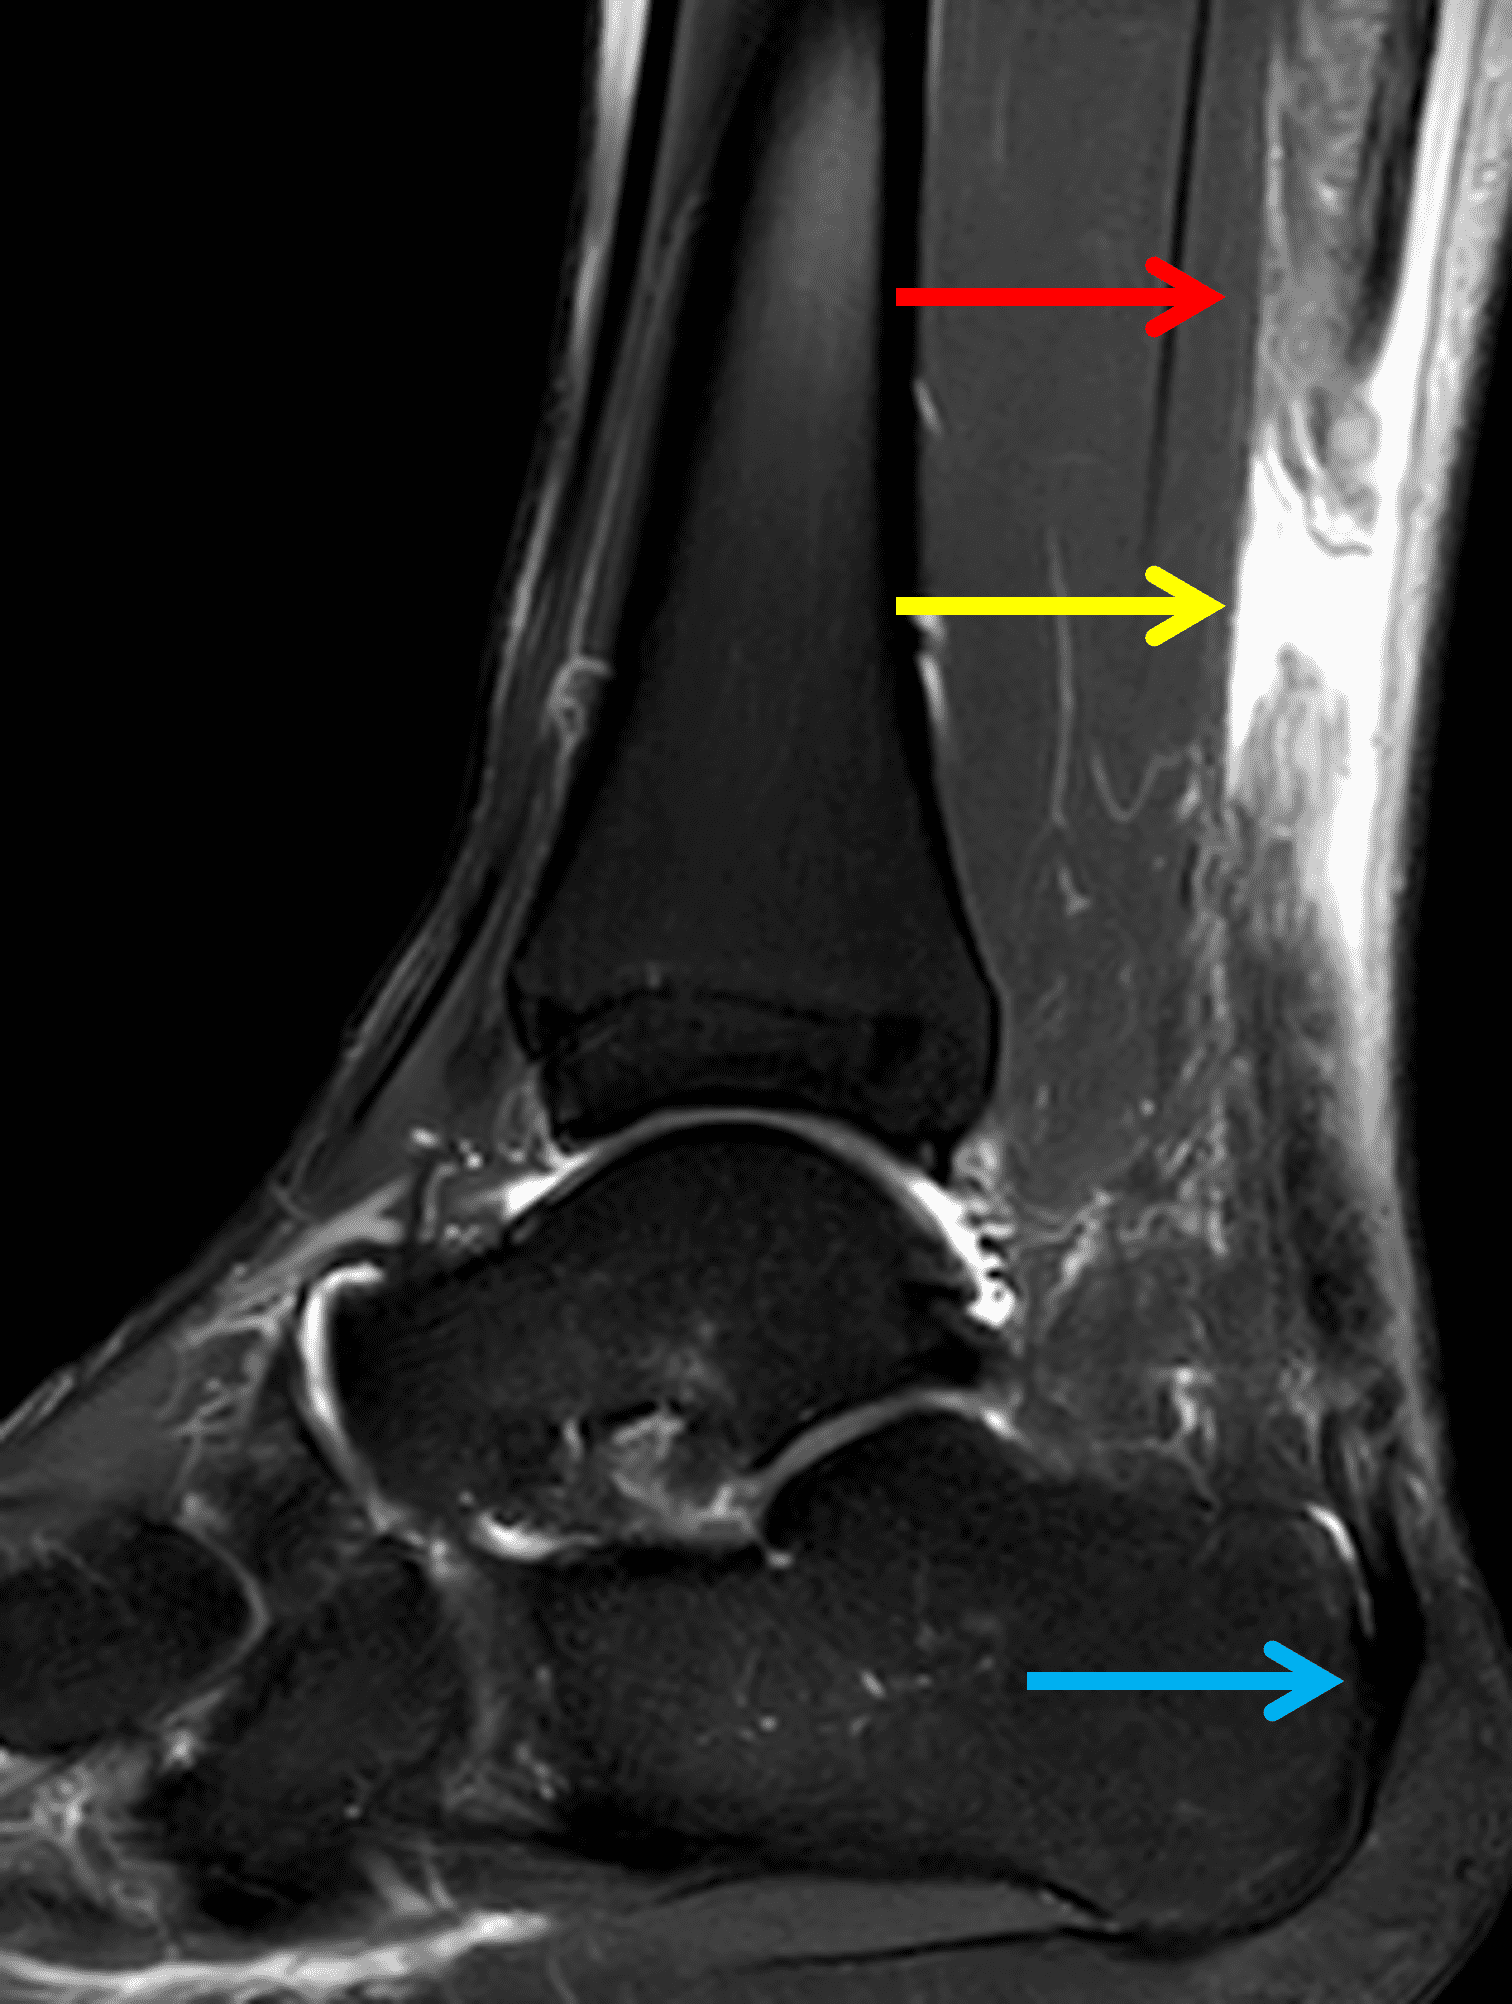

A 22 year-old male college football player presents with a “pop” and pain posterior to the right ankle during practice 1 week prior. He is unable to bear weight. Lateral radiograph (1A), sagittal fat-suppressed T2-weighted (1B), sagittal T1-weighted (1C), and transverse fat-suppressed T2-weighted images are provided. What is your diagnosis? What MRI findings affect clinical management decisions?

Figure 2: Complete Achilles tendon rupture. (2A) The lateral radiograph shows a thick and indistinct proximal Achilles tendon contour (arrows). (2B) A fat-suppressed T2-weighted image shows complete rupture of the tendon with a fluid-filled gap (yellow arrow) measuring 1.5 cm in length, located 10 cm cranial to the tendon insertion (blue arrow) and just distal to the edematous myotendinous junction (red arrow). The tear is superimposed on diffuse tendinosis. (2C) A sagittal T1-weighted image confirms the diffuse tendinosis. Fluid extends anteriorly into Kager’s fat pad (arrow) suggesting disruption of the anterior paratenon. (2D) A transverse fat-suppressed T2-weighted image through the proximal tendon shows no intact fibers (arrow), confirming the full-thickness rupture.